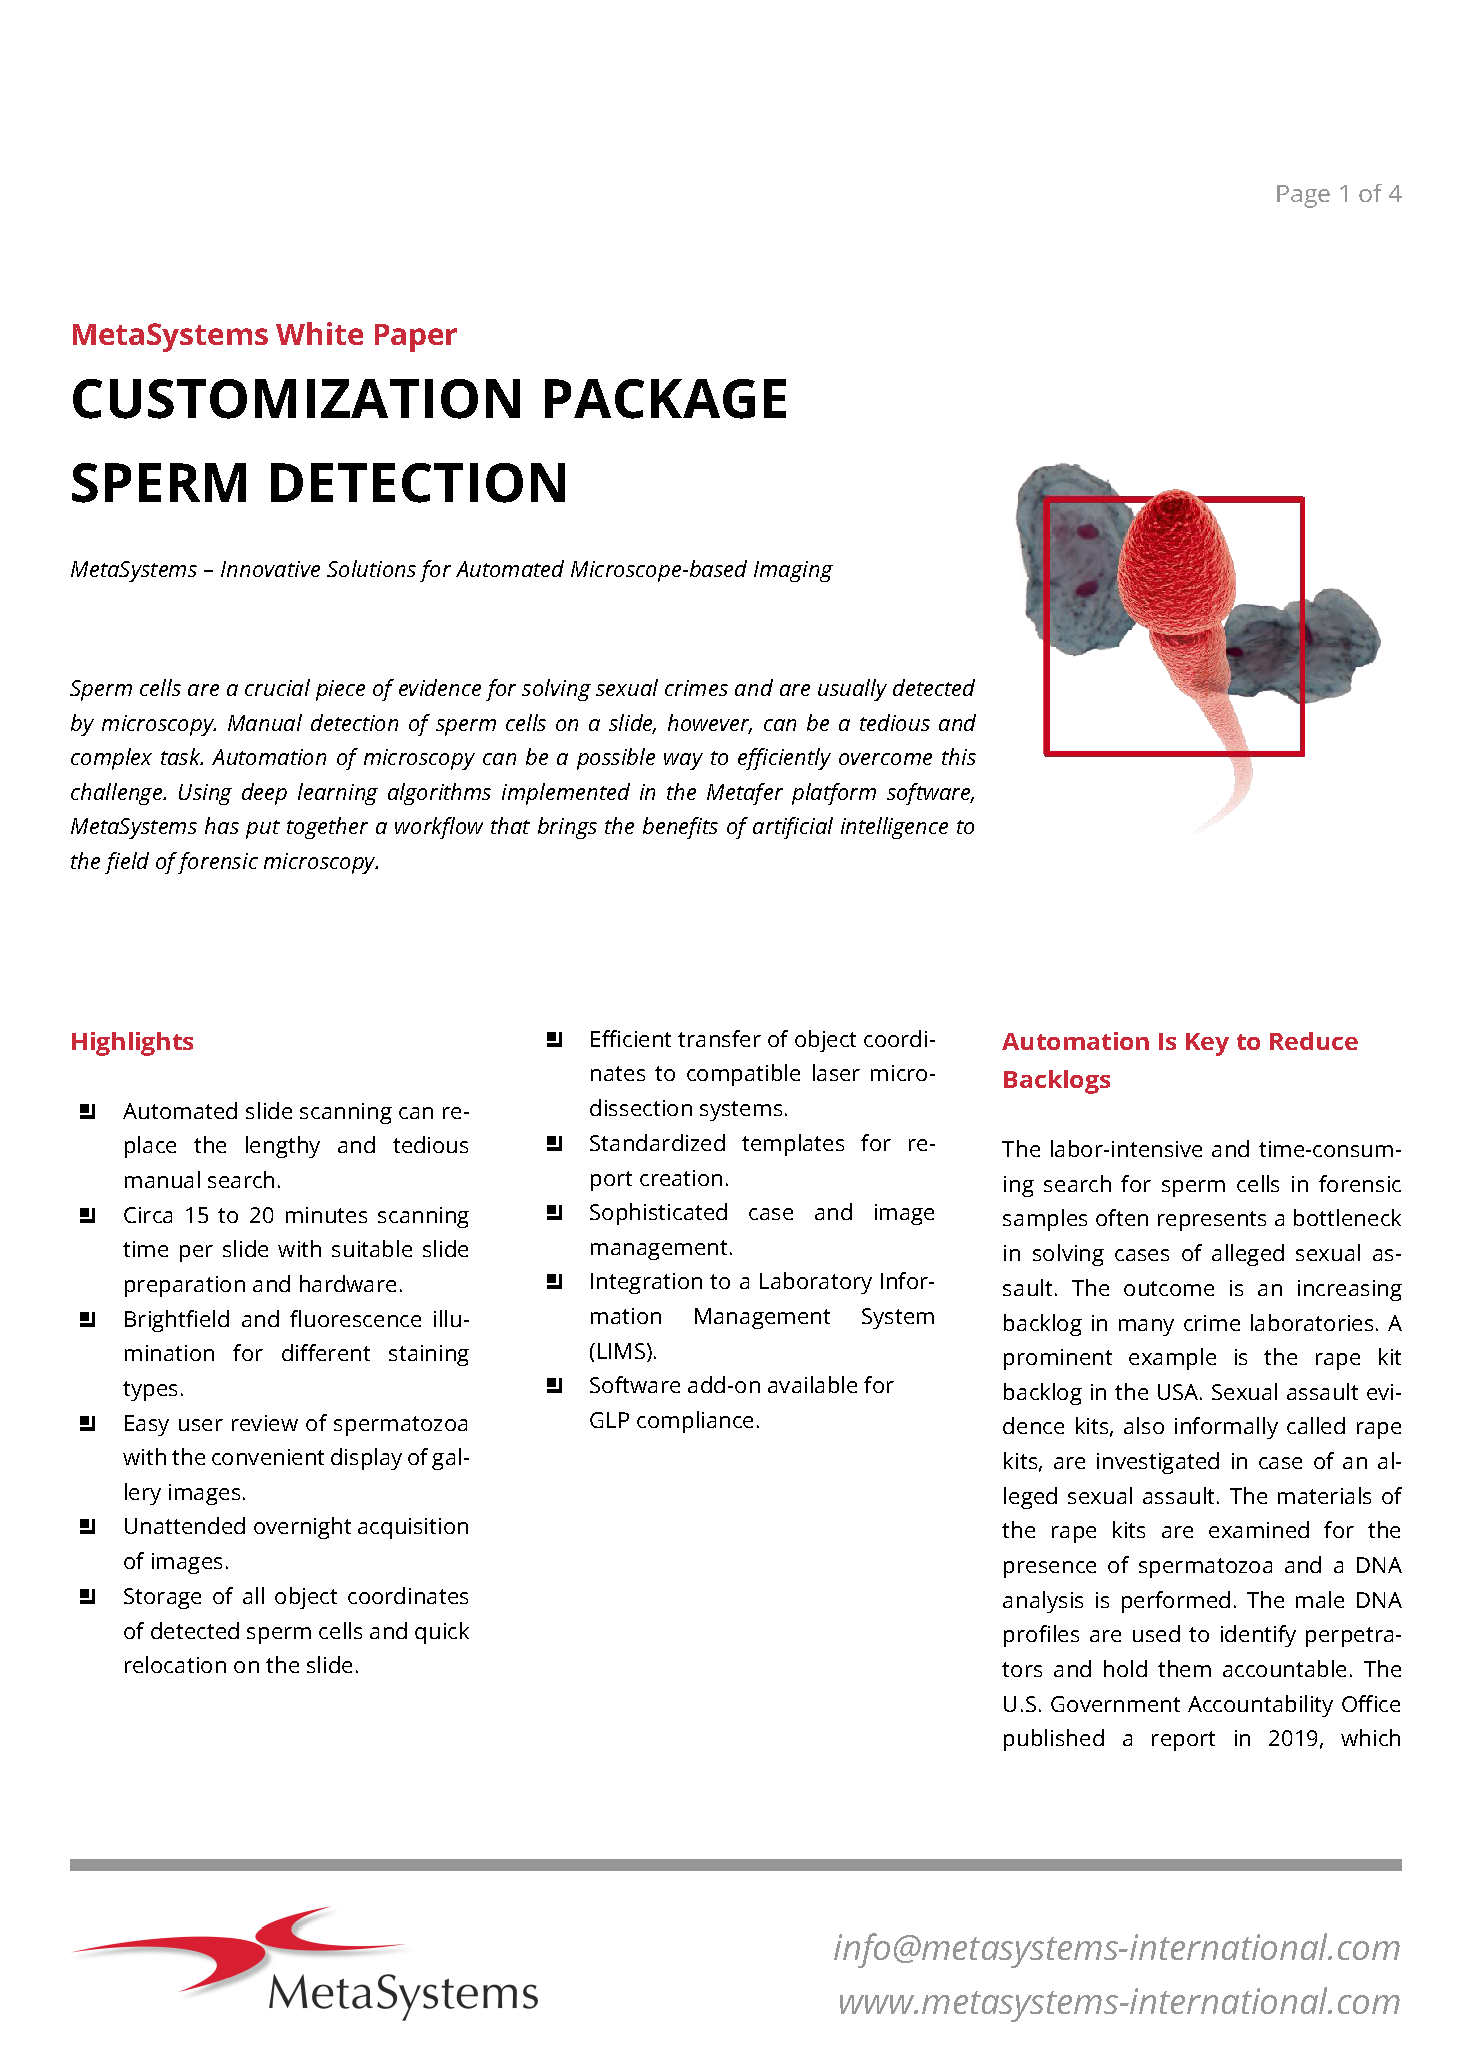

- Customize workflows according to your preferences using a flexible classifier-based imaging approach.

Utilizing the Metafer software, imaging systems scan specimens of diverse sizes, employ various contrasting methods and magnifications, and identify, classify, and enumerate cells or other objects. Metafer's modularity and flexible architecture make it proficient in assisting users from various fields with their specific imaging tasks.

Given the variability of each microscopic sample, automated imaging demands flexibility. Metafer's distinctive concept provides an effective solution: user-trainable classifiers accurately establish imaging standards, and by selecting the relevant classifier, the integrated scanning system swiftly transitions to the next task.

The flexible smart scanning facilitated by Metafer software suggests numerous options, each tailored to specific hardware accessories and software requirements, for various customizations. A variety of software license subsets and hardware options are at your disposal. Commonly, Metafer software-controlled integrated systems consist of one of four camera models and a motorized stage. A fully integrated system requires a motorized microscope. MetaSystems can incorporate the microscope into the installation, although the Metafer software can also be integrated with existing, compatible microscopes.